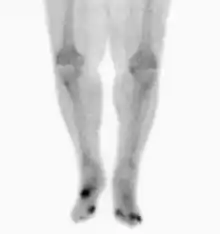

Radiographs and CT are the initial method of diagnosis, but are not sensitive and only moderately specific for the diagnosis. They can show the cortical destruction of advanced osteomyelitis, but can miss nascent or indolent diagnoses.[23]

Confirmation is most often by MRI. The presence of edema, diagnosed as increased signal on T2 sequences, is sensitive, but not specific, as edema can occur in reaction to adjacent cellulitis. Confirmation of bony marrow and cortical destruction by viewing the T1 sequences significantly increases specificity. The administration of intravenous gadolinium-based contrast enhances specificity further. In certain situations, such as severe Charcot arthropathy, diagnosis with MRI is still difficult.[23] Similarly, it is limited in distinguishing avascular necrosis from osteomyelitis in sickle cell anemia.[24]

Nuclear medicine scans can be a helpful adjunct to MRI in patients who have metallic hardware that limits or prevents effective magnetic resonance. Generally a triple phase technetium 99 based scan will show increased uptake on all three phases. Gallium scans are 100% sensitive for osteomyelitis but not specific, and may be helpful in patients with metallic prostheses. Combined WBC imaging with marrow studies has 90% accuracy in diagnosing osteomyelitis.[25]